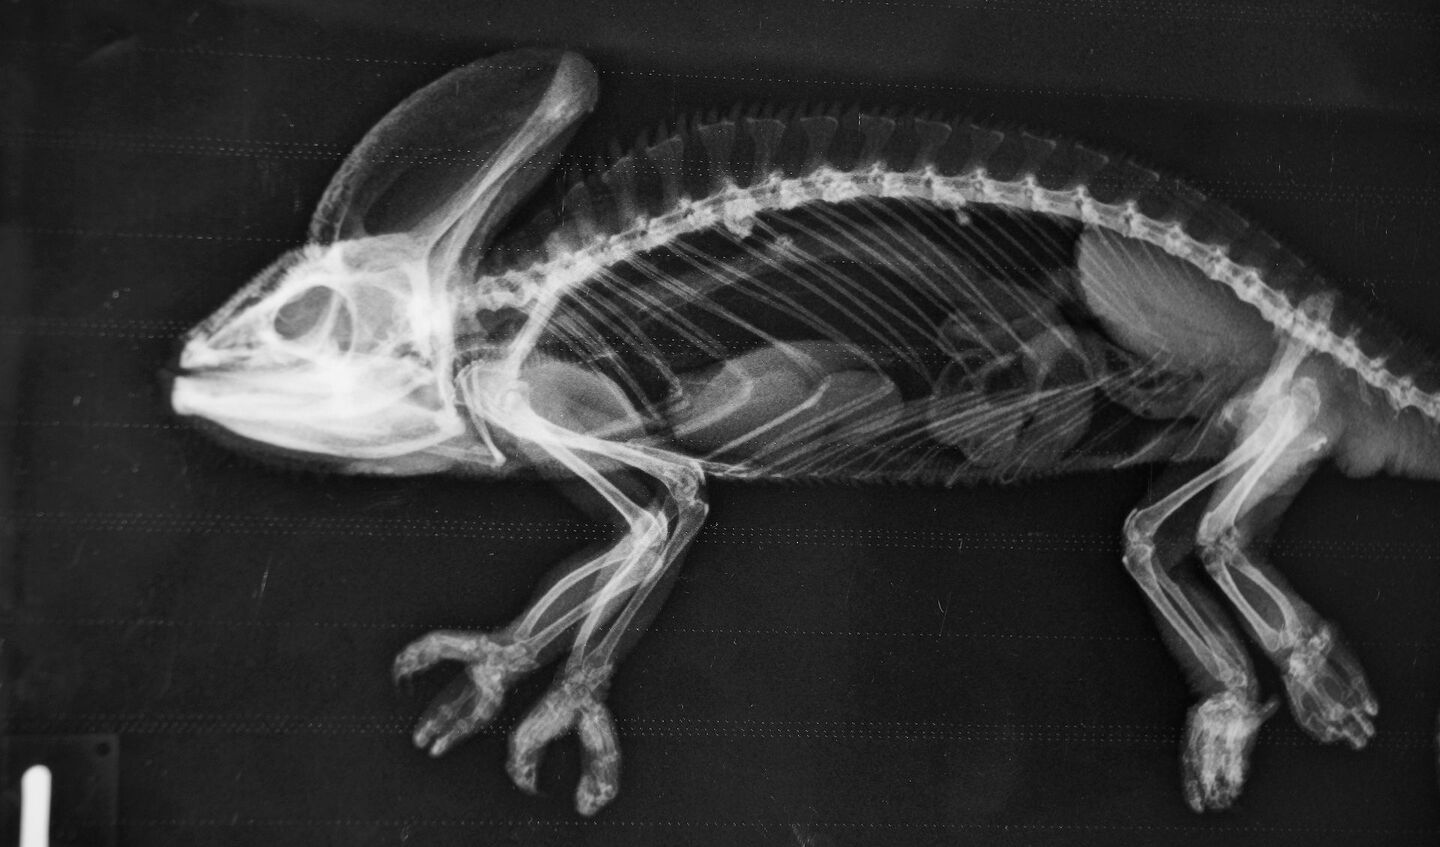

Erstaunlich, das Gerippe eines Seepferdchens! Wie ein Kunstwerk zeigen sich die Knochen, die der Bezeichnung Knochenfische alle Ehre machen. Wundersam wirkt das filigrane Schlangenskelett. Im Röntgenraum der Tierklinik im Basler Zoo wird rasch klar, wie komplex die Arbeit eines Zootierarztes ist. Er muss die Röntgenbilder zahlreicher verschiedener Arten interpretieren. Doch die Schwierigkeit beginnt schon vorher. Wie bekommt man Tiere, vom Seepferdchen bis zum Geparden, auf den Röntgentisch?

Dr. Christian Wenker ist froh über die Möglichkeit, Tiere röntgen zu können. Der leitende Veterinär im Basler Zoo erklärt: «Dank dem bildgebenden Verfahren haben wir in der Zootiermedizin ein rasches Resultat.» Bei Blut- und Kotuntersuchungen müsse bis am nächsten Tag gewartet werden. Schnelles Handeln ist in der Zootiermedizin wichtig. Zeigen Tiere Krankheitssymptome, liegt ein gravierendes Problem vor. Sie verbergen Unwohlsein, denn in der Natur werden schwächelnde Tiere durch Feinde eliminiert.